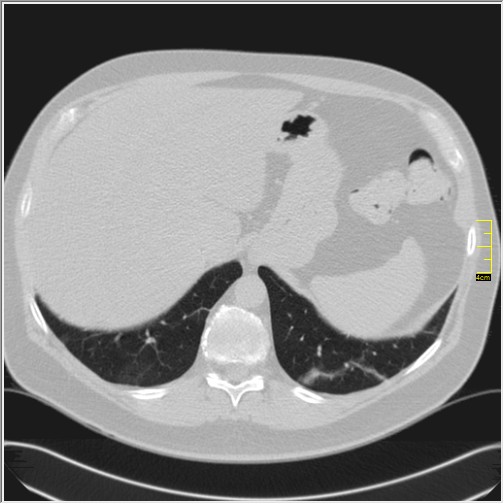

Severity score 0/25. Najdraže mi je kada vidim to.